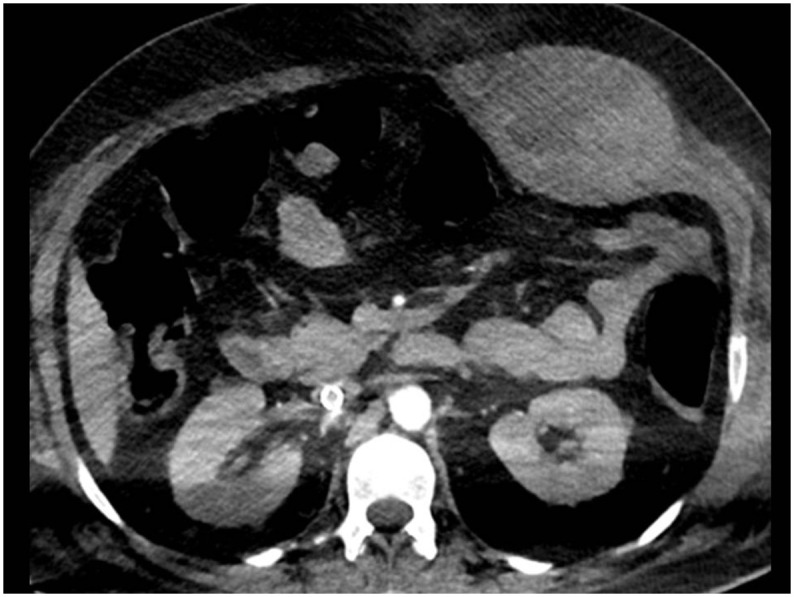

Hemorrhagic complications were diagnosed in 19 patients. The intramuscular hematoma was detected in 17 patients. It involved the iliopsoas compartment unilaterally in 10 patients (Fig. 1 ), bilaterally in 2 patients (Fig. 2 ), and the rectus sheath in 5 cases (Fig. 3 ). Out of these 17 patients, 11 patients were admitted to the ICU. On CT scans, fresh hemorrhage was seen as a discrete mass of high attenuation within the muscle (Fig. 1a). Active contrast extravasation in the arterial phase was detected in 6 patients (Fig. 1b). Pelvic extraperitoneal hemorrhage was found in 3 patients (Fig. 4 ). CT scan in these patients showed large pelvic blood collection. A fluid-fluid level was found in one patient mostly owing to the hematocrit effect (Fig. 4a). Active contrast extravasation in the arterial phase was detected in one patient. Out of these 3 patients with pelvic extraperitoneal hemorrhage, 2 patients had associated intramuscular hematoma (one in the rectus sheath and one in iliopsoas compartments bilaterally). The mesenteric hematoma was diagnosed in one ICU patient. Regarding thromboprophylaxis, 5 patients received the standard prophylactic dose, 4 patients (21.1%) received intermediate-dose thromboprophylaxis and 10 patients (52.6%) received therapeutic dose of anticoagulation.

Fig. 1.

Intramuscular hematoma-Psoas hematoma. (a) Axial non-contrast CT revealed hyperdense fresh hematoma in the right psoas muscle. (b) Axial CTA image revealed sizable left psoas hemorrhage with contrast extravasation suggesting active bleeding.